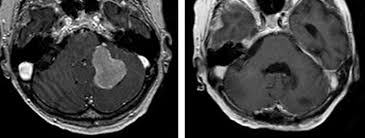

Klinik Und Poliklinik Fuer Neurochirurgie Meningeome